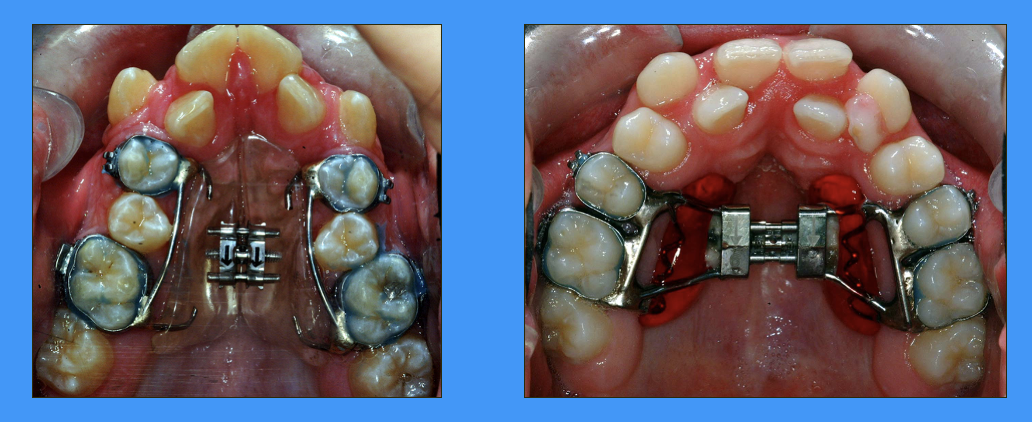

why is knowledge of the growth pattern of the maxilla relevant to dentistry

can incorporate fusion of sutures into treatment for certain patients

expansion of maxilla can be done as a narrow arch can result in crowding of teeth (image)

bone will be laid down at the mid palatal suture - this takes a few months